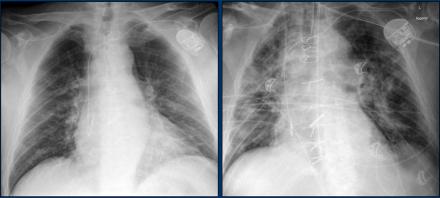

Covid Chest X Ray